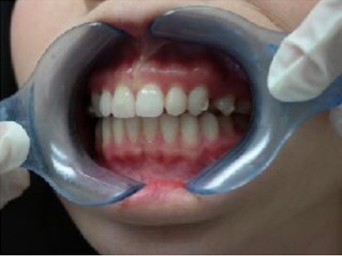

下图是我带上牙套后的样子,基本上是看不出来的,可以说是非常隐形了!

有图有真相

3.15是我安装牙套的第一天,到10.16号已经整整七个月了,不管是牙齿上的改变,和脸部的改变都还蛮大的,许久不见我的朋友都会觉得我变了个人,也很多人说我脸瘦了,其实人家不是胖啦,只是肉很多!不多说,上图

2017.03.15

2017.08.02

2017.10.17

其实还有20个牙套,但是我的凸牙已经基本上都回去了,改变巨大。下面放羞羞的真人图。

比较明显的是我的人中明显变长,嘴突有了很大改善,下巴也因此显得更长,我发现最惊喜的改变是,我的肉肉脸!!!没有了!!!

有人说我瘦了,其实我3月份的时候97斤,现在105斤,所以并不是我的体重,而是我整个脸的变化,我也是有下巴的人了!